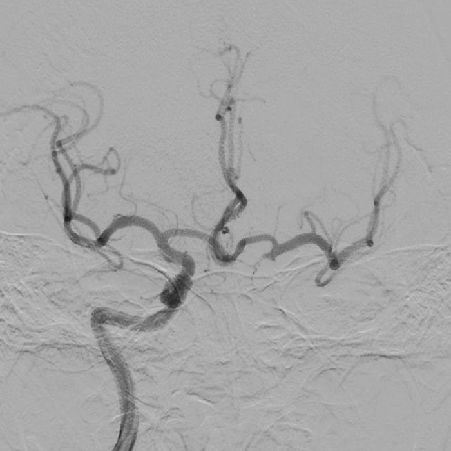

造影可见前交通动脉开放,双侧大脑中动脉显影,左侧颈内动脉末端显影;左侧颈内动脉颈段以远未见显影。

1、造影可见左侧颈总动脉和主动脉弓呈锐角,尝试泥鳅导丝+125cm多功能导管引导8F导引导管超选左侧颈总动脉时,导引导管无法送达,更换6F长鞘超选至左侧颈内动脉颈段,撤出导丝及多功能导管,考虑主动脉弓处张力较大,遂选择具有良好支撑性的React™ 68 远端通路导管替代中间导管。

React™ 68导管内造影见床突段显影浅单,以远未见显影

3、造影可见左侧颈内动脉前向血流恢复,M1段以远显影良好,眼动脉段可见重度狭窄,观察5分钟后,再次造影,眼动脉段以远血流速度明显下降,局部造影剂滞留,考虑与对侧前交通动脉的代偿供血形成湍流,有再次形成血栓的可能,遂对狭窄部位进行球囊扩张。